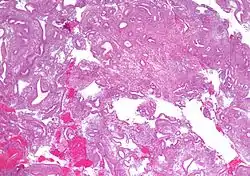

![]() صورة مجهرية showing simple endometrial hyperplasia, where the gland-to-stroma ratio is preserved but the glands have an irregular shape and/or are dilated. خزعة بطانية رحمية. صبغة الهيماتوكسيلين واليوزين. صورة مجهرية showing simple endometrial hyperplasia, where the gland-to-stroma ratio is preserved but the glands have an irregular shape and/or are dilated. خزعة بطانية رحمية. صبغة الهيماتوكسيلين واليوزين. | |